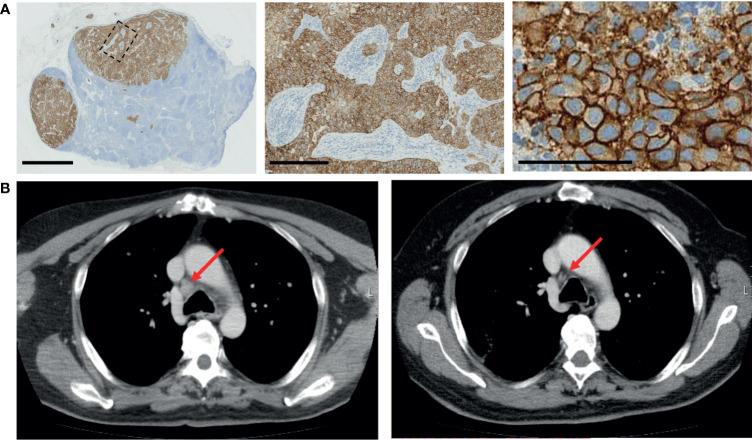

The purpose of drug screening in the context of precision oncology is to serve as a functional diagnostic method for therapy efficacy modeling directly on patient-derived tumor cells. Here, we report a case study using integrated multiomics drug screening approach to assess therapy efficacy in a rare metastatic squamous cell carcinoma of the parotid gland. Tumor cells isolated from lymph node metastasis and distal subcutaneous metastasis were used for imaging-based single-cell resolution drug screening and reverse-phase protein array-based drug screening assays to inform the treatment strategy after standard therapeutic options had been exhausted. The drug targets discovered on the basis of the measured drug efficacy were validated with histopathology, genomic profiling, and cell biology methods, and targeted treatments with durable clinical responses were achieved. These results demonstrate the use of serial drug screening to inform adjuvant therapy options prior to and during treatment and highlight HER2 as a potential therapy target also in metastatic squamous cell carcinoma of the salivary glands.

在精准肿瘤学背景下进行药物筛选的目的是作为一种功能诊断方法,直接在患者来源的肿瘤细胞上建立治疗疗效模型。在此,我们报告一项病例研究,该研究使用综合多组学药物筛选方法评估腮腺罕见转移性鳞状细胞癌的治疗疗效。从淋巴结转移灶和远处皮下转移灶分离出的肿瘤细胞用于基于成像的单细胞分辨率药物筛选和基于反相蛋白阵列的药物筛选试验,以便在标准治疗方案用尽后为治疗策略提供参考。基于测得的药物疗效发现的药物靶点通过组织病理学、基因组分析和细胞生物学方法进行验证,并实现了具有持久临床反应的靶向治疗。这些结果证明了使用系列药物筛选在治疗前和治疗期间为辅助治疗方案提供参考,并突出了HER2作为唾液腺转移性鳞状细胞癌潜在治疗靶点的作用。